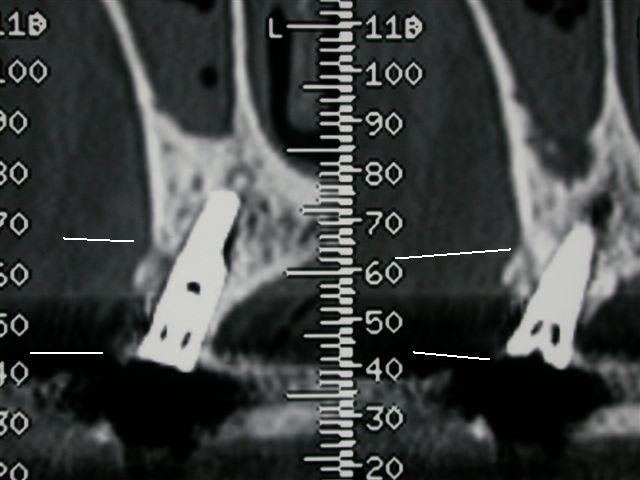

un petit cas ou par chance il y a eu un scan après la pose d'un implant avec bio-oss + mb résorbable juste coincée dans la vis de l'implant avec un point en bretelle, on voit bien le remaniement osseux et l'os néoformé avec un aspect différent au scan

il faut effectivement qu'il y ait un apport trophique, comme il est abscent en vestibulaire à cause de la mb, une cavité où coincer le bio-oss est necessaire avec des parois osseuses et non cementaires

Voici l' autre cas dont je parlais...où scan et aspect sont top,mais où la sonde montre que ça reste un matériau cicatriciel non réellement ossifié, peu dense...par contre,c'est vrai qu' il maintient le volume, reste parfaitement intégré, et joue son role esthétique...

quid dans 15 ans?